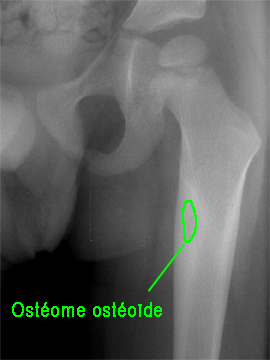

Les pathologies tumorales localisées :

Bénignes :

Ostéome ostéoïde, dysplasie fibreuse,…